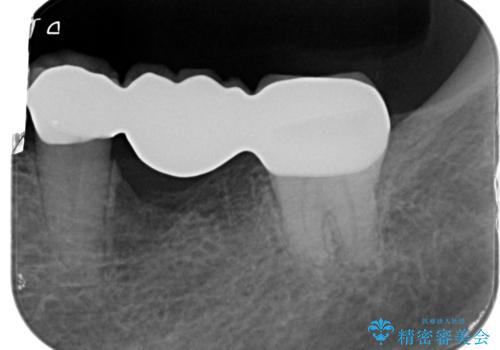

- 39.6万円(ジルコニアクラウン×3・仮歯×3)費用は治療当時の料金となります

前後の歯も一緒に審美性を回復することができ、喜んでいただくことができました。